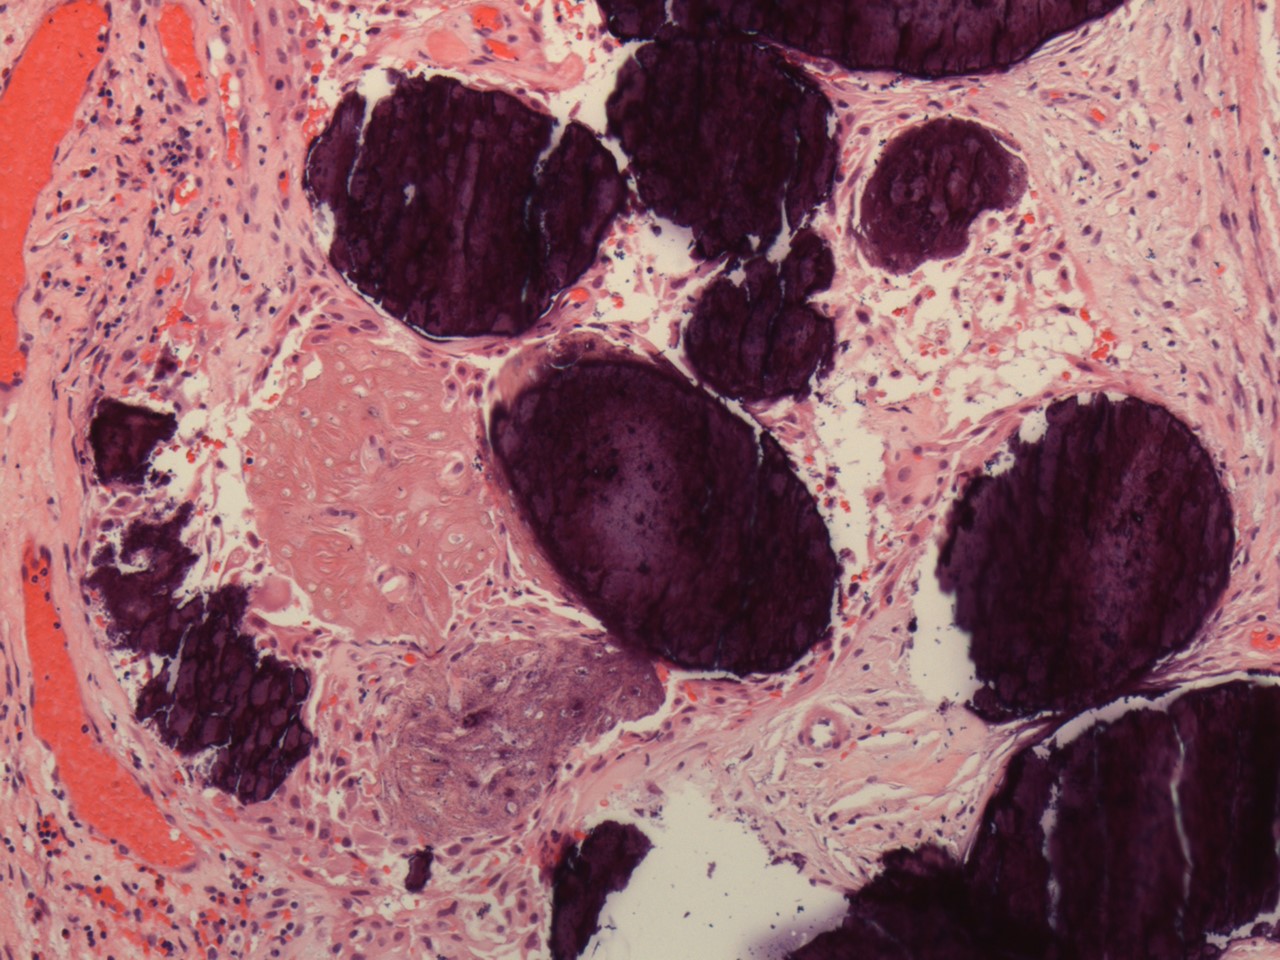

A 40 y/o euthyroid female and a 3 cm left-sided thyroid nodule incidentally found.